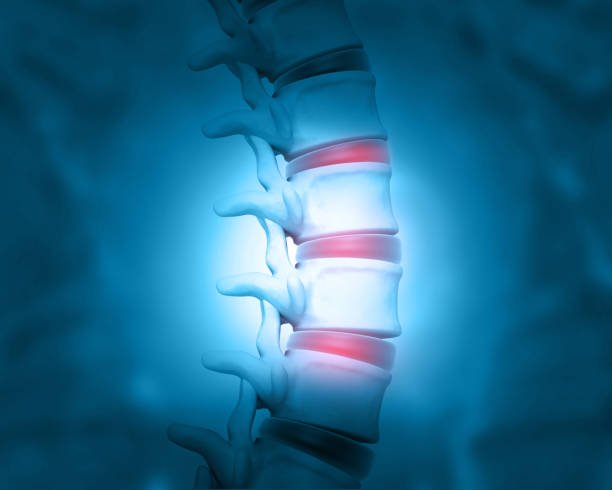

Back Pain

Back pain physiotherapy relieves discomfort, improves posture, strength, flexibility, mobility, and promotes long-term spinal health.

Disc Bulge

Disc bulge physiotherapy relieves nerve pain, improves spinal alignment, mobility, strength, and prevents recurrence safely.